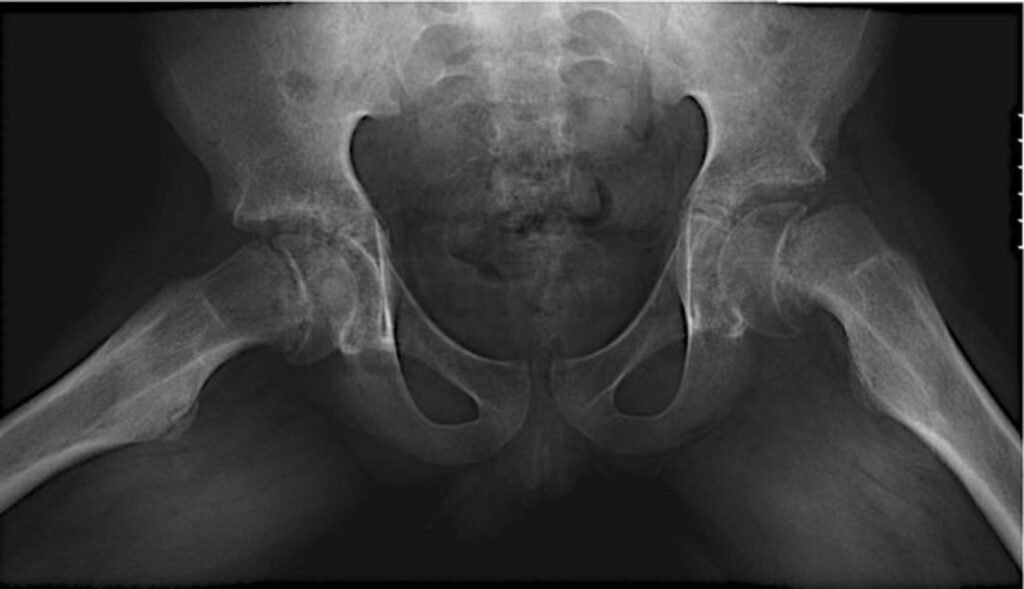

O diagnóstico é confirmado por exames de imagem, principalmente radiografias específicas do quadril.